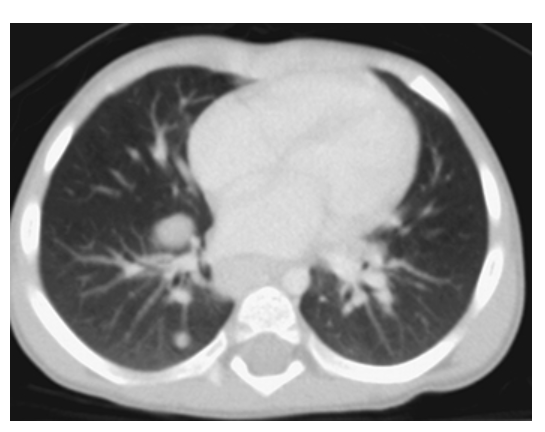

Histoplasmosis. Axial CT shows multiple well-defined subcentimeter calcified nodules in the lungs and mediastinum as a result of prior histoplasmosis infection.